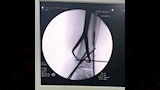

وتضمنت الإصابات كسرًا مضاعفًا في مركز النمو أسفل عظمة القصبة اليسرى، وكسرًا أسفل عظمة الشظية اليسرى، وخلعًا كاملًا في مفصل الكاحل الأيسر، وفقًا لخطورة الإصابات وتأثر مركز النمو، سارع الفريق الطبي إلى اتخاذ قرار بالتدخل العاجل منعًا لتأثير مستقبلي على حركة الطالب أو نمو العظام.

ونجح الفريق في رد الخلع بشكل فوري، أعقبه إجراء عملية تثبيت جراحي للعظام باستخدام أسلاك معدنية، وسط متابعة دقيقة لضمان إعادة العظام إلى موضعها الطبيعي وتفادي أي مضاعفات محتملة، إذ أسهمت سرعة التدخل ودقته في استقرار حالة الطالب سريعًا، قبل أن يغادر المستشفى في حالة جيدة بعد تلقيه الرعاية الطبية الكاملة.